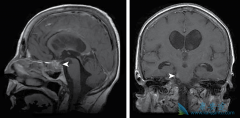

• 什么是肺癌脑转移以及肺癌脑转移症状有哪些

什么是肺癌脑转移以及肺癌脑转移症状有哪些

什么是肺癌脑转移?脑转移瘤系指原发于身体其他部位的肿瘤细胞转入颅内,其发病率占颅内肿瘤的3.5%-10%,目前以 肺癌脑转移 最多见。非小细胞肺癌在作出诊断时约有20%的患者已有脑转移,而非小细胞肺癌患者在病程中约有30%左右发生脑转移,其中以大细胞 ...

• 关于肺癌脑转移放疗联合靶向治疗的介绍

关于肺癌脑转移放疗联合靶向治疗的介绍

对于 EGFR 突变和 ALK 重排非小细胞肺癌(NSCLC), 肺癌脑转移 (BM)是诊断和复发时的第二常见部位。25%~50% NSCLC 在整个疾病过程中出现BM。30%~60% EGFR 突变、40%~70% ALK+ 患者发生 BM。BM 影响生存期和生活质量,预期生存期(OS)3~15 个月。 ...

• 不同组织类型的患者肺癌脑转移能活多久有差异

不同组织类型的患者肺癌脑转移能活多久有差异

肺癌发展到了晚期,经常会出现转移,根据转移的不同部位,会产生不同的症状,而超过一半的肺癌可能出现脑转移,那么,出现 肺癌脑转移能活多久 ?肺癌脑转移患者预后差,自然平均生存时间仅 1~2 个月。专家表示,肺癌脑转移是晚期肺癌较常出现的现象。 ...